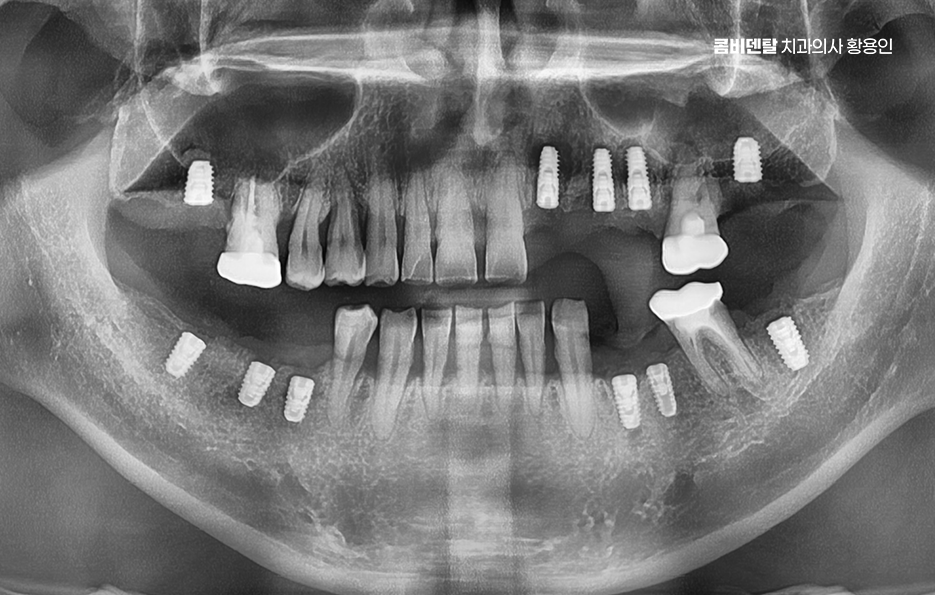

치아 발치 후 임플란트 치료 과정은 처음에 CT나 파노라마 엑스레이를 통해 뼈의 양과 밀도, 신경 위치를 정확히 확인하는 것부터 시작되며 치아가 빠진 자리에 뼈가 많이 흡수되어 있다면, 임플란트를 심기 전에 뼈이식을 먼저 해야 할 수 있지만 반대로 뼈 상태가 좋다면 임플란트를 심고, 보통 3개월 동안 뼈와 잘 붙을 때까지 골융합 과정을 기다리게 되며 골융합이 잘 이루어진 뒤에는 그 위에 지대주라는 연결 부품을 끼우고, 그 위에 최종 보철물을 씌우면서 치료가 마무리되고 있어요